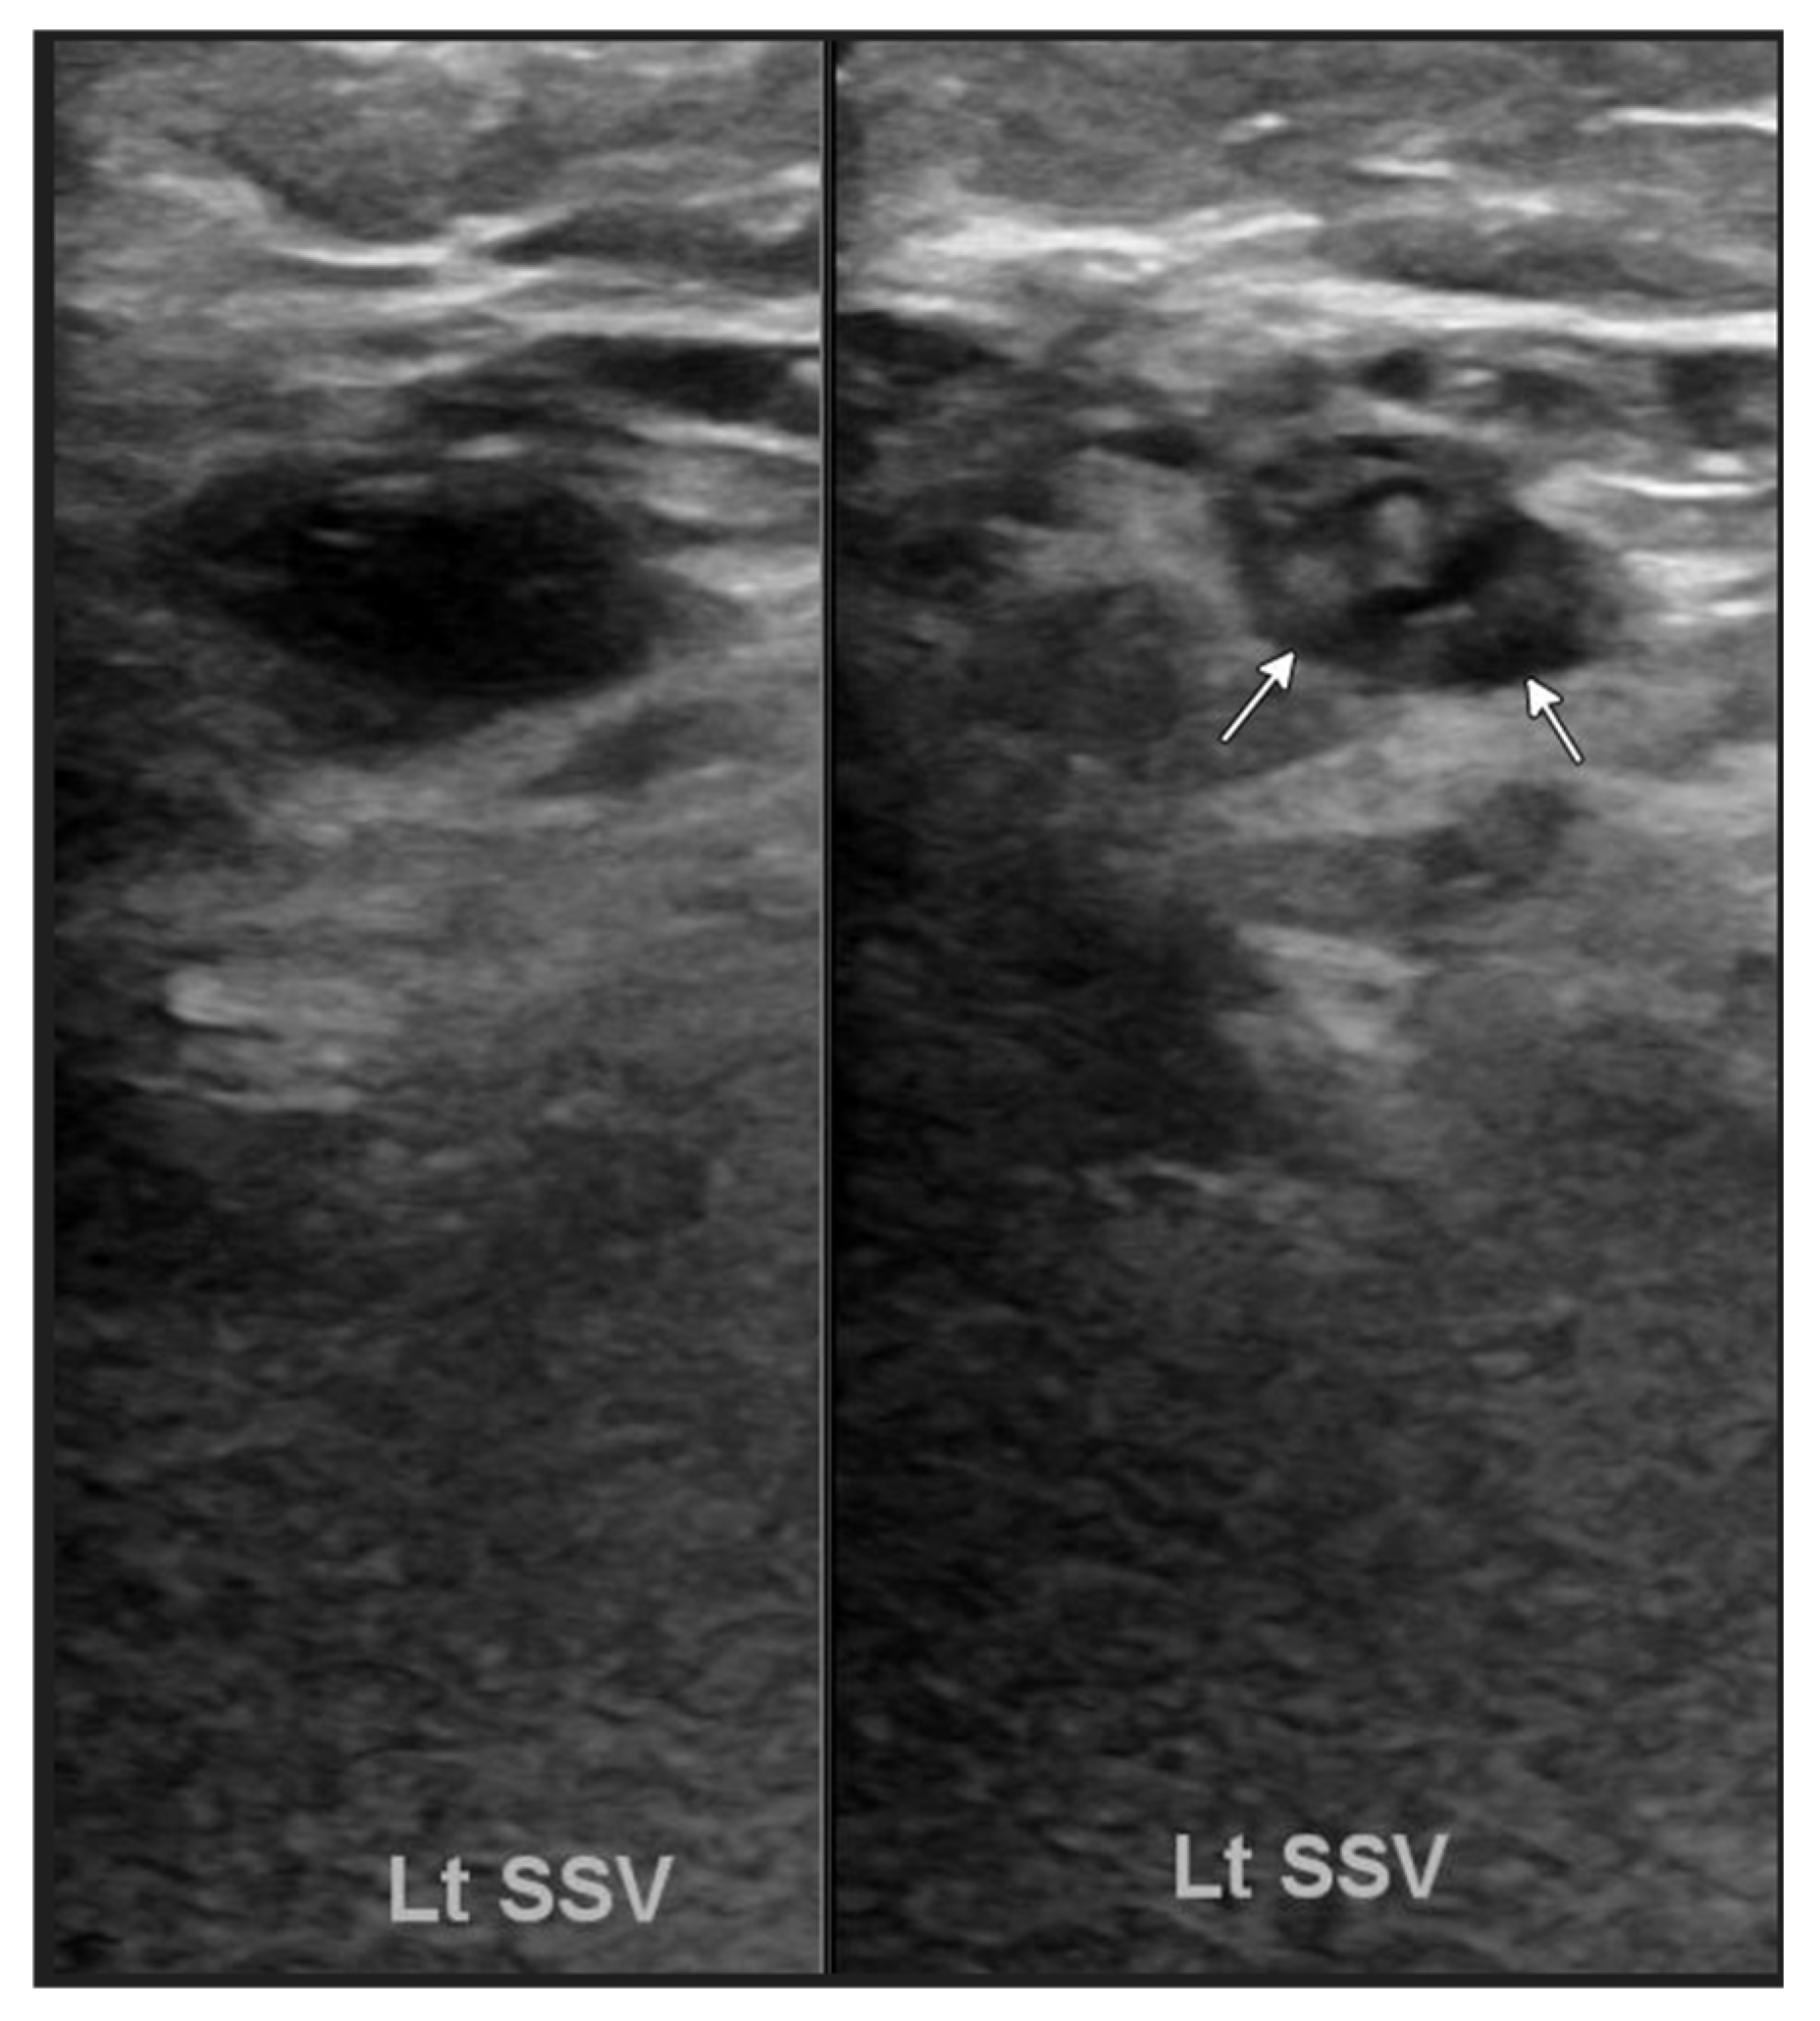

Initial laboratory results showed lactate levels of 2.6 mmol/L (reference range: 0.5–2.2 mmol/L), Troponin-T of 35 ng/L (reference range: ≤15 ng/L), B-type natriuretic peptide (BNP) of 1852 pg/mL, prothrombin time (PT) of 13.2 s (reference range: 9–13 s), and international normalized ratio (INR) of 1.2 (reference range: 0.8–1.2). An ultrasound of the left lower extremity, with and without compression applied, revealed a nonocclusive superficial venous thrombus in the left small saphenous vein (Figure 2). Chest X-ray revealed a stable enlarged cardiac/pericardial silhouette and stable mediastinal contours. An electrocardiogram (EKG) revealed sinus tachycardia with ventricular pacing and premature ventricular contractions. The echocardiogram revealed a significantly enlarged left ventricular chamber size with the presence of regional wall motion abnormalities (basal septal akinesis/dyskinesis) with a left ventricular ejection fraction of 28%. Additionally, left ventricular internal diameter was 59 mm in diastole, 51 mm in systole, and severe mitral valve regurgitation was identified. Basal septal akinesis/dyskinesis further raised concerns for possible CS. Right heart catheterization demonstrated elevated pressures, with a right atrial pressure of 9 mmHg, right ventricular pressure of 42/12 mmHg, pulmonary artery pressure of 38/27 mmHg (31 mmHg), and pulmonary capillary wedge pressure of 24 mmHg, indicative of acute heart failure.

Figure 2.

Ultrasound of the left lower extremity with and without compression applied demonstrates a nonocclusive superficial venous thrombus in the left small saphenous vein (arrows).